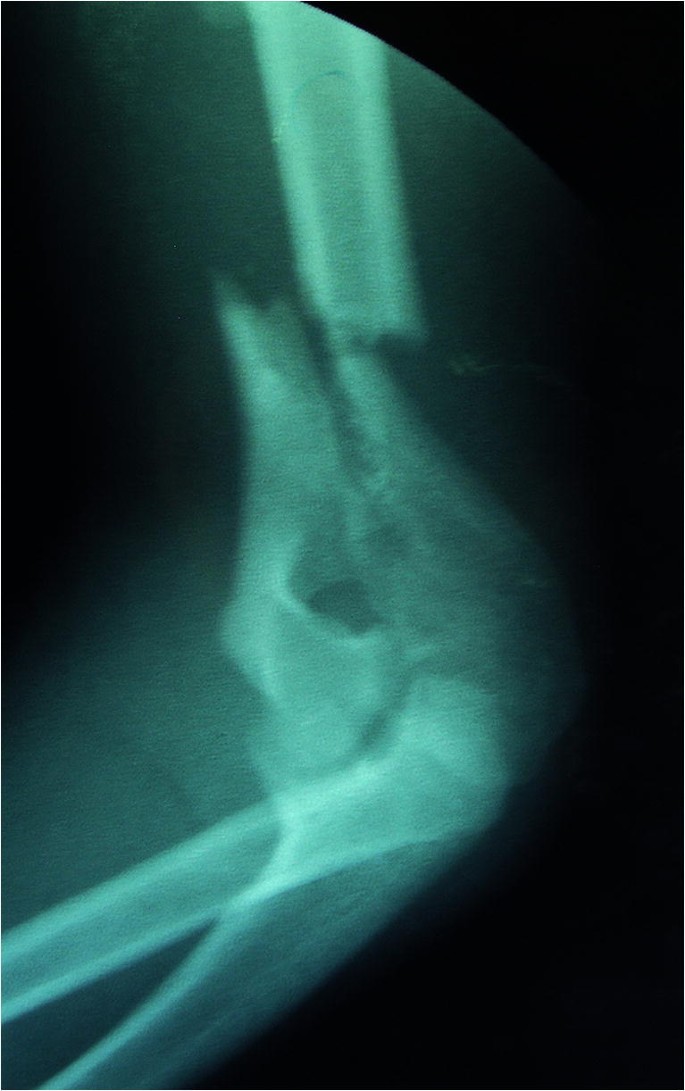

S40S49 Injuries to the shoulder and upper arm ;. Comminuted T condylar fracture of the left distal humerus is noted with intraarticular extension Posterior displacement of the distal fragment is seen in the sagittal plane;. By definition, Tcondylar fractures are intraarticular, distal humerus fractures characterized by a central intercondylar split and extension of the fracture line proximally through both the medial and lateral columns Tcondylar fractures in children are rare elbow fractures and are, perhaps, the most challenging to manage.

Pediatric Tcondylar humerus fractures requiring an open approach may benefit from less invasive approaches such as the triceps split approach where the fracture pattern allows Younger children are more amenable to less invasive means of fracture reduction and fixation If an articular reduction is required, the aggregated literature suggests that the Morrey slide offers equivalent results to the olecranon osteotomy but with fewer approachrelated complications. Blakey CM, Biant LC, Birch R Ischaemia and the of elbow fracture in children analysis of 355 pink, pulseless hand complicating supracondylar fractures, with special reference to supracondylar fractures of the humerus in childhood longterm humerus fractures. With mild lateral/valgus displacement and rotation is noted in the coronal plane No radial or ulnar fracture is notedSoft tissue swelling is noted around the elbow.